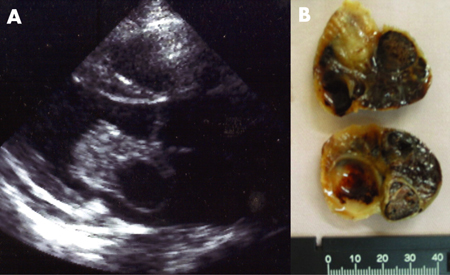

[Figure caption and citation for the preceding image starts]: Two-dimensional echocardiogram showing a right atrial mass suggestive of a myxomaFrom the collection of Dr Syed Wamique Yusuf, Department of Cardiology, University of Texas MD Anderson Cancer Center; used with permission [Citation ends].

[Figure caption and citation for the preceding image starts]: Atrial myxoma identified on echocardiography (A) and following surgical resection (B)From: HH Ho, WK Seto, E Wang, WH Chow. BMJ Case Reports 2009; doi:10.1136/bcr.2006.093781 [Citation ends].